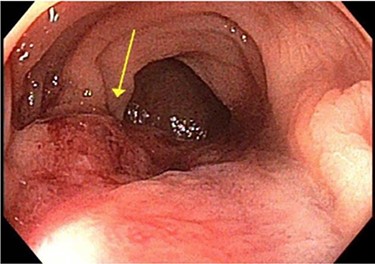

Surveillance colonoscopy in 2018 identified a fungating nonobstructing mass in the sigmoid colon (Fig. 1). Histology from a biopsy showed poorly differentiated carcinoma (Fig. 2). Given the history of breast cancer, further immunohistochemical staining was performed, which was positive for E-cadherin (Fig. 3), ER (Fig. 4), PR, GATA3 binding protein (GATA 3) (Fig. 5) and negative for Cytokeratin 20 (CK20) (Fig. 6). This confirmed metastatic invasive ductal carcinoma of breast. A positron emission tomography (PET) scan showed only the retroperitoneal mass involving the proximal sigmoid colon with no other evidence of metastatic disease (Fig. 7).